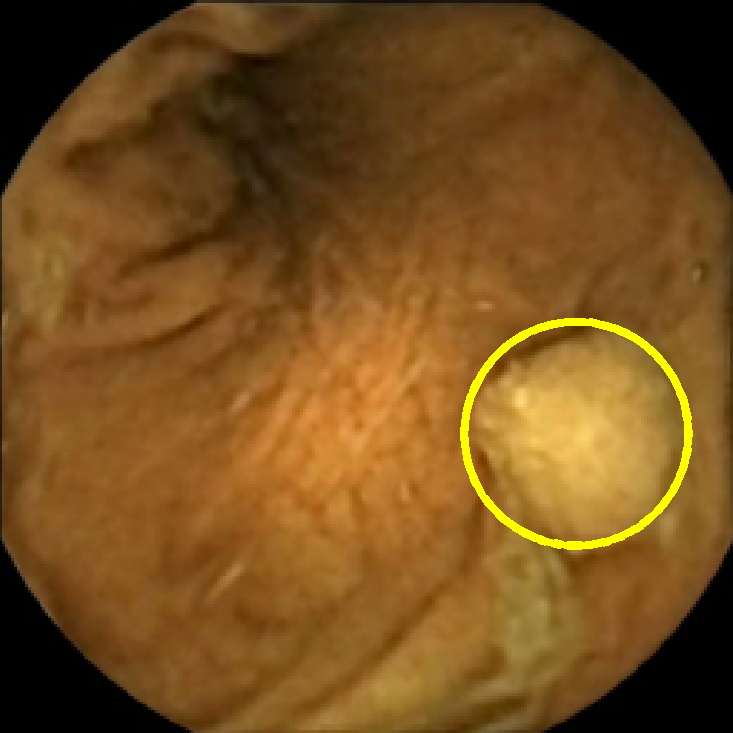

In Figure 5 we show the circles of radius corresponding to the features that were correctly classified as polyps by (29). We observe that the classifier was able to identify the polyps of a variety of shapes even in the presence of small amounts of trash liquid (first row) or when the polyps are located next to mucosal folds (rows two to four in column (c)).

The examples of incorrect classification of frames are presented in Figure 6. The first two examples show false negatives, each highlighting a possible source of classification error. The example in column (a) shows the case where the feature corresponding to the polyp was too stretched out and thus was rejected by the eccentricity criterion (21). In contrast, the feature corresponding to the polyp in column (b) has passed the combined geometric criterion (22), but the radius was below the threshold of the binary classifier. Examples in columns (c) and (d) show the two sources of possible false positives. The false positive detection in column (c) is due to insufficient illumination correction. The bright spot is not fully corrected at the pre-processing stage and subsequently generates a polyp-like feature in the mid-pass filtered frame that happens to pass through all the criteria. Finally, in column (d) a mucosal fold is classified as polyp. Note that such cases are the most difficult to deal with, as the mucosal folds can often be hard to distinguish from polyps even for a human operator.